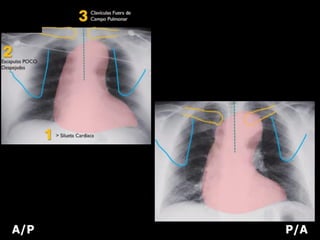

POSTEROANTERIOR (PA)

• ESCÁPULA: Periferia del tórax

• CLAVÍCULAS: Dentro de los campos

pulmonares, la región medial super

impuesta a la 3a o 4a costillas.

ANTEROPOSTERIOR (AP)

• ESCÁPULA: Sobre los campos

pulmonares

• CLAVÍCULAS: Sobre los ápices

• Magnificación de la silueta cardiaca

A/P P/A